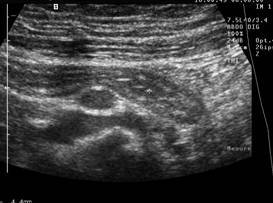

Compresia gradata sonografica este sugestiva pentru stabilirea cu acuratete a diagnsticului de apendicita. Apendicele apare ca o terminatie oarba, un fragment intestinal neperistaltic, cu originea la nivelul cecului. Printr-o compresiune maximala, se masoara diametrul antero-posterior al apendicelui. Testul este considerat pozitiv daca diametrul antero - posterior al apendicelui necomprimat este de 6 mm sau mai mult. Prezenta unui apendicolit stabileste diagnosticul. Imaginea ecografica a unui apendice normal, care este o structura tubulalara inchisa la un capat, usor compresibila, cu un diametru de 5 mm sau mai putin, exclude diagnosticul de apendicita acuta. Studiul este considerat negativ daca apendicele nu se vizualizeaza si nu exista o masa tumorala sau fluid pericecal. Cand se exclude ecografic diagnosticul de apendicita acuta, o scurta evaluare a restului cavitatii abdominale ar fi de preferat pentru stabilirea unui alt diagnostic. La femeile active sexual, organele pelvine genitale ar trebui vizualizate atat transabdominal, cat si transvaginal, pentru a exclude o patologie ginecologica care ar putea cauza durerea abdominala acuta.

Diagnosticul ecografic al apendicitei acute are o sensibilitate de 78 - 96 % si o specificitate de 85 - 98 %. Ecografia poate fi realizata in scop diagnostic la copii si femeile insarcinate, desi aplicabilitatea ei este oarecum limitata in ultimele luni de sarcina.

Ecografia are o serie de limite nete si rezultatele sunt dependente de experienta celui care o efectueaza. O imagine fals pozitiva poate sa apara in prezenta unui proces inflamator periapendicular determinat de inflamatia tesuturilor limitrofe; o dilatare a trompelor uterine poate fi confundata cu o inflamatie apendiculara, resturi de fecale neevacuate pot mima un apendicolit, iar la pacientii obezi, apendicele poate fi incompresibil atat datorita procesului inflamator acut, dar si datorita stratului de tesut adipos. Ecografii fals negative pot sa apara in conditiile unei limitari a procesului inflamator la varful apendicelui, in apendici cu localizare retrocecala, atunci cand este marit si poate fi confundat cu intestinul subtire sau in caz de perforatie apendiculara cand este comprimat.

Fig. 10 Apendicita acuta cu adenopatie inflamatorie

Fig. 12 Apendicita acuta ( diametru transvers >6mm